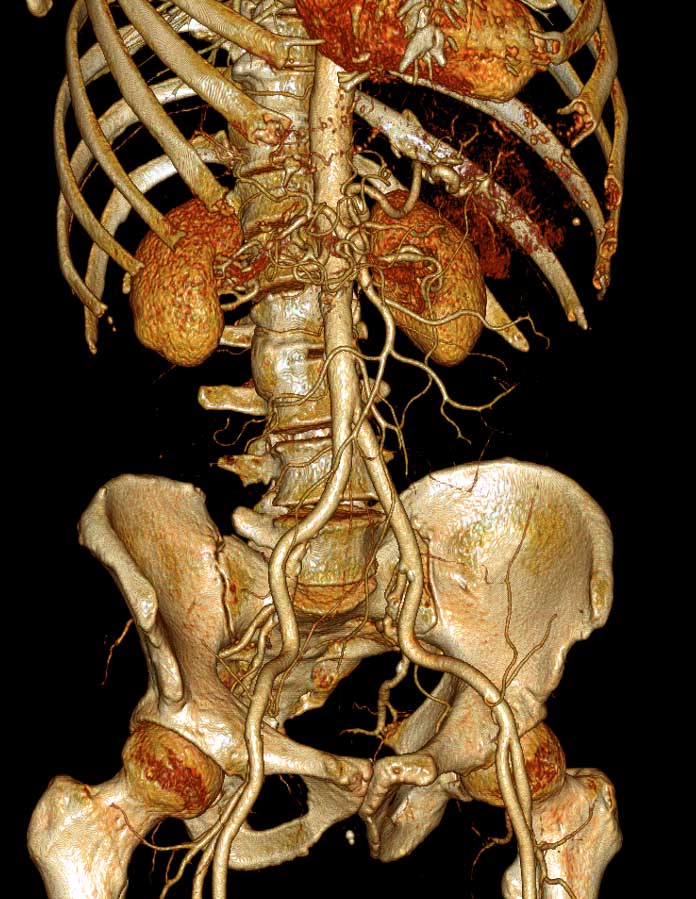

мСКТ, СКТА, МРТ, МРА, рентгенография, маммография

128-срезовом мультиспиральном рентгеновском компьютерном томографе

Как и в любых других видах диагностического поиска при радиологическом обследовании, например, мультиспиральной компьютерно-томографической (мСКТ) или магнитнорезонанской (МРТ) томографии, процедура проводится не для того, чтобы найти что-нибудь (не важно что), хотя в процессе проведения случайные находки и встречаются. Основная цель – подтверждение или опровержения наличия вполне определенных изменений. В связи с этим, перед проведением диагностики настоятельно рекомендуется проконсультироваться с врачом.

В отличии от электрофизиологических и ультразвуковых методик, радиологические предоставляют информацию, которая может быть качественно документирована в общепринятых международных форматах. Именно это обстоятельство делает возможным отсроченный анализ томограмм, рентгеновских снимков и т.д., который многие грамотные специалисты предпочитают осуществлять самостоятельно.

Качественная диагностика, тем не менее, складывается из уровня и характеристик используемого оборудования и квалификации персонала (не только врача-рентгенолога, но и лаборантов и техников, т.к. важно получить качественные изображения, пригодные для дальнейшего анализа).